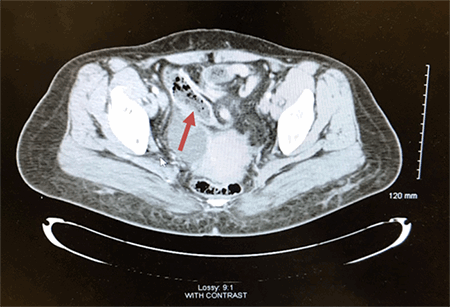

A 48-year-old female with a past medical history of diabetes mellitus presented with abdominal pain. She reported that for the past two days, she had worsening abdominal pain. The pain was localized to her right and left lower quadrants, without radiation and not associated with oral intake. The pain was rated 8/10 and was described as a sharp pain that was constantly present. She also complained of chills and nausea, but no vomiting. She denied diarrhea, any recent falls or injury, and any exposure to ill contacts. On physical exam, her vital signs were pulse 83, respirations 18 and blood pressure 102/59. The abdomen was soft, without rebound or guarding. A positive McBurney’s point and positive obturator sign was noted, with a negative Psoas sign. On admission, her white blood cells were normal at 5.7 but trended up to 18.7 about 14 hours afterwards. Her hemoglobin, and basic biochemistry panel were within normal limits. CT of the abdomen and pelvis with contrast showed findings consistent with acute distal appendicitis. The distal 3 cm of the appendix was thickened to 1.3 cm, fluid-filled and showed adjacent stranding. The segment of distended appendix was seen located within the right anterior paracentral pelvis approximately 3 cm above the umbilicus (Figure 1 and Figure 2). We can also see the sigmoid colon on the right and cecum in the middle of the body (Figure 3).

Figure 3. Malrotation of the sigmoid colon and cecum